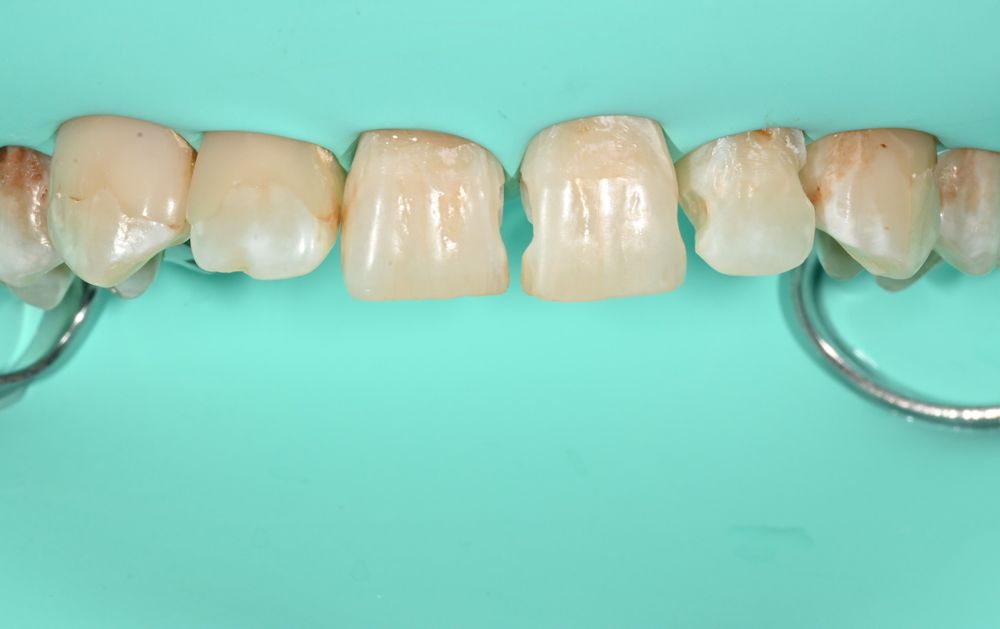

Пациент жаловался, что зубы выглядят неэстетично и иногда реагируют болью на холодное. При осмотре и по результатам компьютерной томографии мы обнаружили скрытый кариес на передних зубах на контактных поверхностях — его почти не было видно невооруженным глазом. Темные пятна на передних поверхностях зубов оказались врожденным дефектом эмали — гипоплазией. Боли они не причиняли, но пациенту не нравился внешний вид улыбки.

Мы провели лечение под местной анестезией и с использованием коффердама, который изолирует зубы и создает сухое и чистое рабочее поле. Это важно: во влажной среде пломбировочные материалы держатся хуже, и результат служит меньше.

За один визит, всего за полтора часа, мы полностью устранили проблему: пролечили скрытый кариес и закрыли дефекты эмали современными композитными материалами, точно подобрав цвет и восстановив форму зубов.